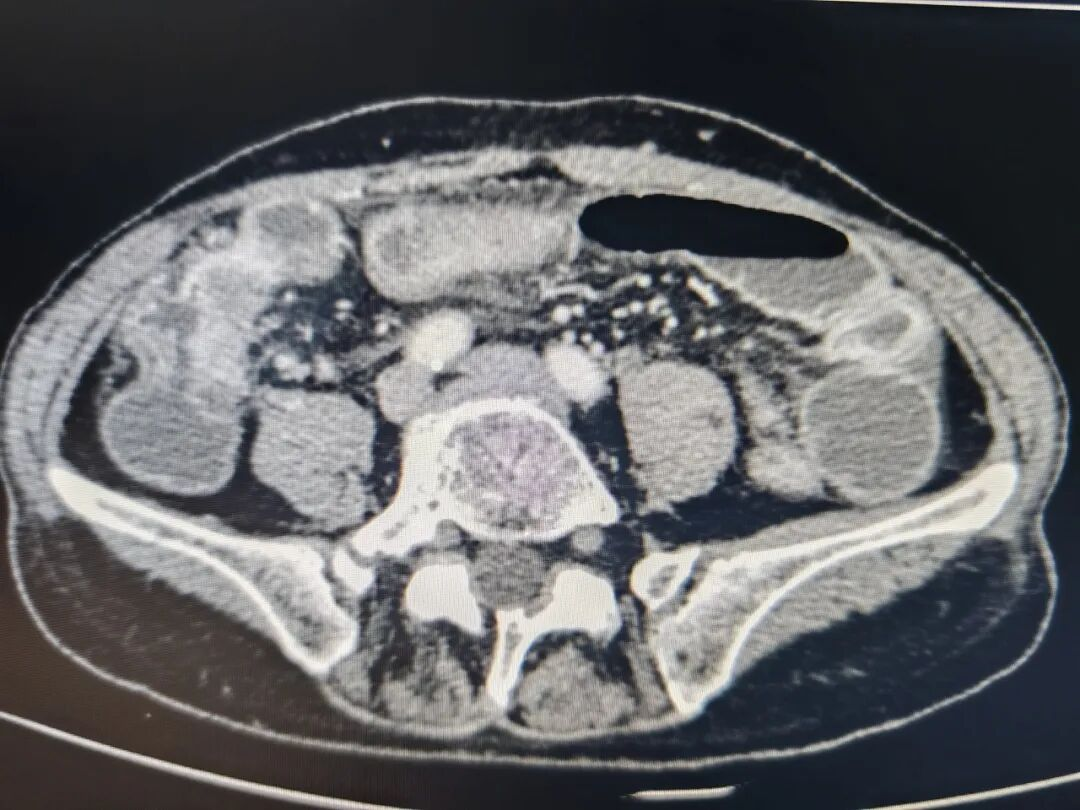

微创介入手术中

方案虽好,但难题是将支架放入回盲部。回盲部处于大肠和小肠的交界处,深藏肠道远端,常规肠镜难以抵达,更难以通过狭窄的回盲瓣进入回肠,又因为肠道长期梗阻严重扩张、形态扭曲,常规斑马导丝支撑力弱、质地偏软,想要将支架精准送到梗阻部位,技术难度太大。

此时,消化内科的“助攻”成为关键,乔京贵主任团队凭借肠镜优势,为介入科提供实时导航。一场“消化科引路、介入科操作”的联合手术展开。乔京贵主任操作肠镜,一点点探查通路,李瑞军主任借助肠镜置入超滑导丝至升结肠处,退出肠镜后再经导丝置入导管,将导丝经回盲部肿瘤调整至回肠末端,造影,明确梗阻部位、长度,交换斑马导丝,沿导丝精确释放支架,成功把肿瘤“推回去”。

放置导管处